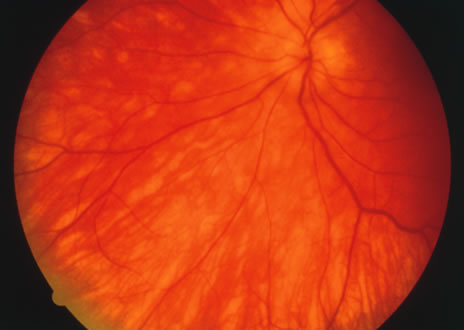

The classic fundus findings are small (500 μm), ill-defined, and sometimes difficult to see grayish-white dots that are dispersed throughout the posterior pole. These spots rarely may become confluent and if this occurs to spots that are around the disc, it may present as a case of giant blind spot syndrome or of an entity that probably is a variant of MEWDS called AZOOR.8 In addition to the dispersed small spots, there is a fine granularity of the fovea. This finding is pathognomonic for this disease, and it can exist in the absence of the white dots (Figs. 1 and 2).

Fig. 1. Color fundus photograph of a patient with multiple evanescent white dot syndrome. Notice that the foveal spot and irregularity is much easier to detect than the subtle white dots.